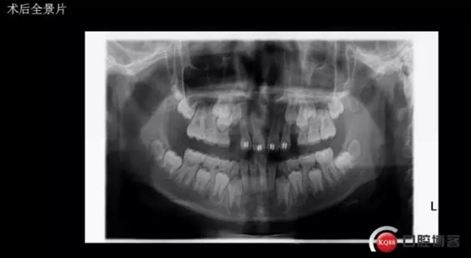

術后思考:患兒如今已經(jīng)十一歲多, 雖然已經(jīng)給尖牙騰出了位置,然而全景片顯示兩顆尖牙位置依然很深,是主動出擊還是靜觀其變呢?歡迎大家共同探討!